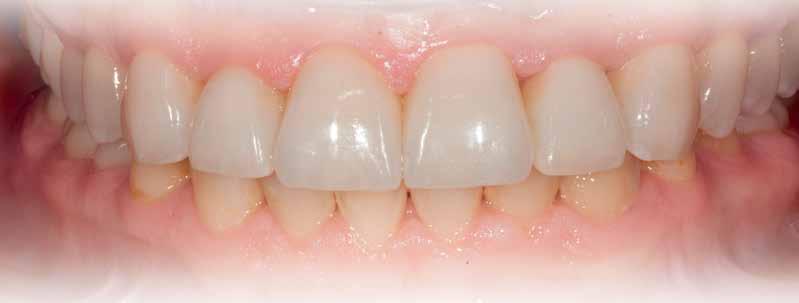

Splinted porcelain fused-to-metal crowns were created for teeth #9-#11, a single PFM crown was fabricated for tooth #6 and splinted, cementretained crowns, incorporating pink ceramics were designed for the two implants (Figs 19,

Figure 19: Conventional, PFM crowns are fabricated for the 4 natural teeth in the premaxilla. Soft tissue colored ceramics are used on the right canine, as well as the implantretained restoration to compensate for vertical discrepancies between the right and left sides of the esthetic zone.

20A, 20B). A periapical radiograph demonstrated crestal bone present at the level of the implant platforms, suggesting successful regeneration and osseointegration (Fig. 21).

Figure 20A: Final restorations in place

Meeting the patient’s esthetic expectations are at least as challenging as the clinical procedures often faced surgically and prosthetically. In order to provide a result, the patient will be satisfied with, even when heroic surgical treatment has been accomplished, we must depend on the prosthetic team to make up for any deficiencies surgery did not accomplish. These scenarios could be for example due to the type of defect, loss of adjacent periodontal ligament and existing blood supply, thus resulting in some instances in different bone height and corresponding soft tissues. Among the prosthetic objectives for the final restoration are: duplication of color, shape, translucency and texture. Even when these previous concepts are accomplished, patient’s expectations may still not be met, especially when the resulting crown will have a long gingival-incisal anatomy. Therefore, to overcome this problem, and with the attempt to have a correct proportion between the final restoration and adjacent teeth, pink porcelain or composite is often utilized, thus enabling us to have the appearance of a normal size tooth with the correct proportion as it relates to adjacent teeth and just as important to be pleasing to the patient’s smile.26-30